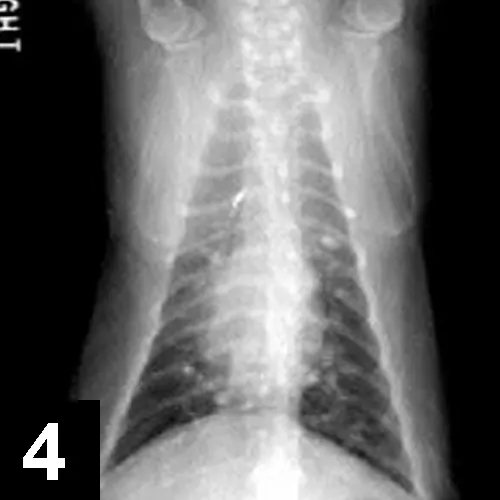

Diagnostics: CBC, chemistry panel, urinalysis, FeLV/FIV serologic testing, fecal analysis, and thoracic radiographs (Figures 1 and 2) were done initially (Table).

The cat is suspected of having underlying allergic airway disease, although this was not proven. Eosinophils were present in the nasal passages, airways, and blood and are commonly encountered in allergic disease. The mineralized pulmonary nodules seen on thoracic radiographs were thought to be due to dystrophic mineralization of chronically inflamed airways, although granulomas or metastatic disease could not be definitively ruled out.

Interpretation: Multifocal, mineralized, well-circumscribed nodules throughout the lung fields. A diffuse, moderate bronchointerstitial pattern is also present.